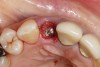

Fig 1. Clinical photograph showing significant issues related to implant midfacial mucosal recession and loss of interdental papillae. This is attributed to incorrect implant positioning (too buccal and too deep); several corrective surgeries resulted in interproximal bone loss, then loss of interdental papillae.

Figure 1

A minimum of 2 mm of facial bone thickness has been proposed as the “critical bone thickness” for the prevention of vertical height loss of the facial plate. It has been reported that when the distance of the buccal shoulder position of the implant to facial bone plate is below this critical thickness, an increased amount of facial bone resorption may be observed, which, in turn, may increase the chance of implant mucosal recession and failure (Figure 1). When the facial bone thickness is more than 2 mm from the implant buccal shoulder position, the likelihood of facial bone loss is decreased and the chance for alveolar bone stability is, therefore, increased.16

Chen and coworkers evaluated the soft-tissue and radiographic outcomes of implants placed in extraction sockets using a nonsubmerged protocol. The result showed statistically significantly higher marginal tissue recession at sites when implants were placed 1.1 mm from the inner buccal socket wall compared with implants placed 2.3 mm from the inner buccal socket wall. Six of the eight implant cases that were buccally positioned had unsatisfactory post-restorative esthetic outcomes. The authors concluded that position of the implant shoulder within the socket is a critical factor for ideal esthetic outcomes; thus, a minimum of 2 mm distance from the implant shoulder to the inner buccal shoulder wall was recommended to prevent implant marginal tissue recession.5